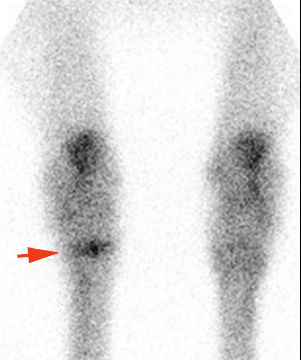

Szcintigráfia

A szcintigráfia egy olyan vizsgálati módszer, melynél egy speciális radioaktív anyagot juttatunk a páciensbe. Nem kell megijedni, hiszen nem csernobili uránt, amelyik még a ló unokáiban is fellelhető lesz, hanem teknéciumot, aminek a felezési ideje (sugárzási ideje) nagyon rövid, mintegy 6 óra. De addig hasznunkra válhat, hiszen kötődik különböző szövetekhez és ott felhalmozódva sugárzik, amit egy speciális kamerával (gamma kamera) detektálni tudunk. Az ortopédiában elsősorban olyan eseteknél használjuk, ahol nem lehet pontosan meghatározni a fájdalom helyét, vagy egyéb módszerrel nem tudunk vizsgálni. Leginkább a hát, a kereszttájék és a végtagok felső részeinek problémáinál használjuk, de repedések kimutatásánál is hasznos lehet.

A csánk sziluettjét láthatjuk. A piros nyíl a csánkízületi gyulladás helyét mutatja.